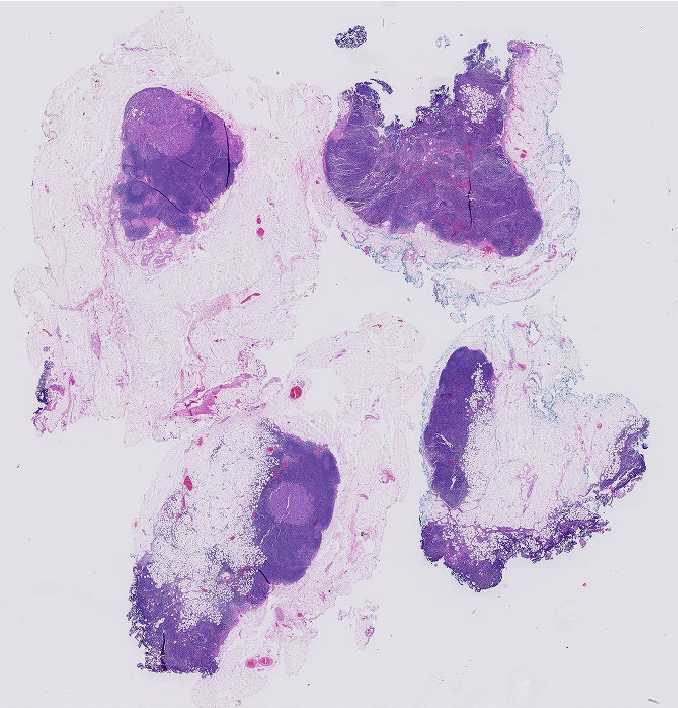

Tumour burden is defined as the ratio of the viable tumour region to the whole tumour region. The viable tumour region is defined as the cancerous region. The whole tumour area is defined as the outermost boundary enclosing all the dispersed viable tumour cell nests, tumour necrosis, and tumour capsule (Fig 2). Each tissue sample contains only one whole tumour region. This metric has applications in assessing the response rates of patients to cancer treatment.

Fig. 13 shows the results obtained using the proposed methodology described in section 3.10. In (a) the predicted whole tumour segmentation was similar to pathologist provided ground truth of whole tumour region and most of the samples in the dataset fell into this category. The proposed methodology for the whole tumour region failed in following cases where - (b) the predicted viable tumour regions were scattered into small discrete disjoint regions which were distant from the most prominent viable tumour region and (c) the whole tumour region was larger than the convex hull of the viable tumour region.